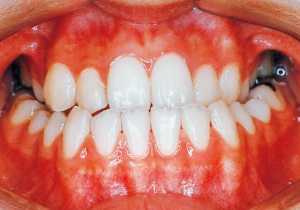

Age at Initial Visit: 8 years 1 month, Female / Protruding lower bite. Protruding lower jaw

This case presented with Class III malocclusion and significant negative overjet from the early mixed dentition. Regular observation was conducted, and Phase I treatment was initiated after the eruption of the anterior teeth, improving the anterior occlusal relationship and molar relationship. Subsequently, regular observation continued toward the completion of the permanent dentition. However, due to vigorous mandibular growth, orthodontic treatment including surgery became necessary.

Although there were many missing deciduous teeth, the number of permanent teeth was not problematic (4). The amount of negative overjet was significant (1). On cephalometric radiographs, the mandibular ramus was not relatively long, but the large gonial angle and the long mandibular body were noticeable, indicating an overall tendency of the mandible to project inferiorly and anteriorly. High lower facial height was also characteristic.

A potential predisposition to mandibular protrusion was clearly evident.